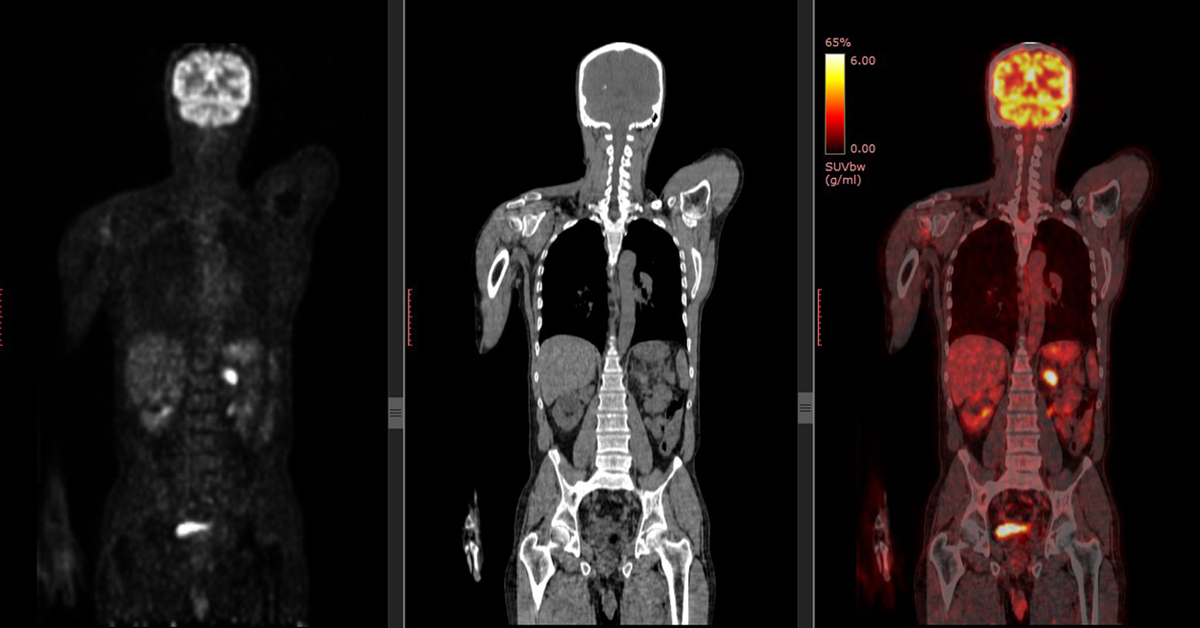

The tracer will collect in areas of higher chemical activity, which is helpful because certain tissues of the body, and certain diseases, have a higher level of chemical activity. These areas of disease will show up as bright spots on the PET scan.

Different colors and degrees of brightness on the scan will indicate different levels of tissue function, helping the patient and doctor decide how best to move forward.

PET scans show metabolic changes occurring at the cellular level in an organ or tissue. This is important because disease often begins at the cellular level. CT scans (and MRIs) can’t reveal problems at the cellular level.

PET scans can detect very early changes in a patient’s cells. CT scans (and MRIs) can only detect changes later, as a disease alters the structure of your organs or tissues.

Perhaps the main difference between a CT scan and a PET scan is their focus. A CT scan creates a de-tailed non-moving image of organs, bones, and tissues. A PET scan, on the other hand, shows doctors how the tissues in a patient’s body work on a cellular level. Other important differences include:

- They use different materials: CT scans pass x-rays through the body to create images. A PET scan uses a radioactive material which emits energy. The energy is then detected by a special camera to produce images.

- PET scans detect cancer earlier than other tests: Unlike other forms of imaging, a PET scan shows molecular activity and helps doctors identify diseases in the earliest stages. For this rea-son, a PET scan is a highly reliable tool for detecting cancer. CT scans show signs of an issue after a disease begins to change the structure of tissues or organs.